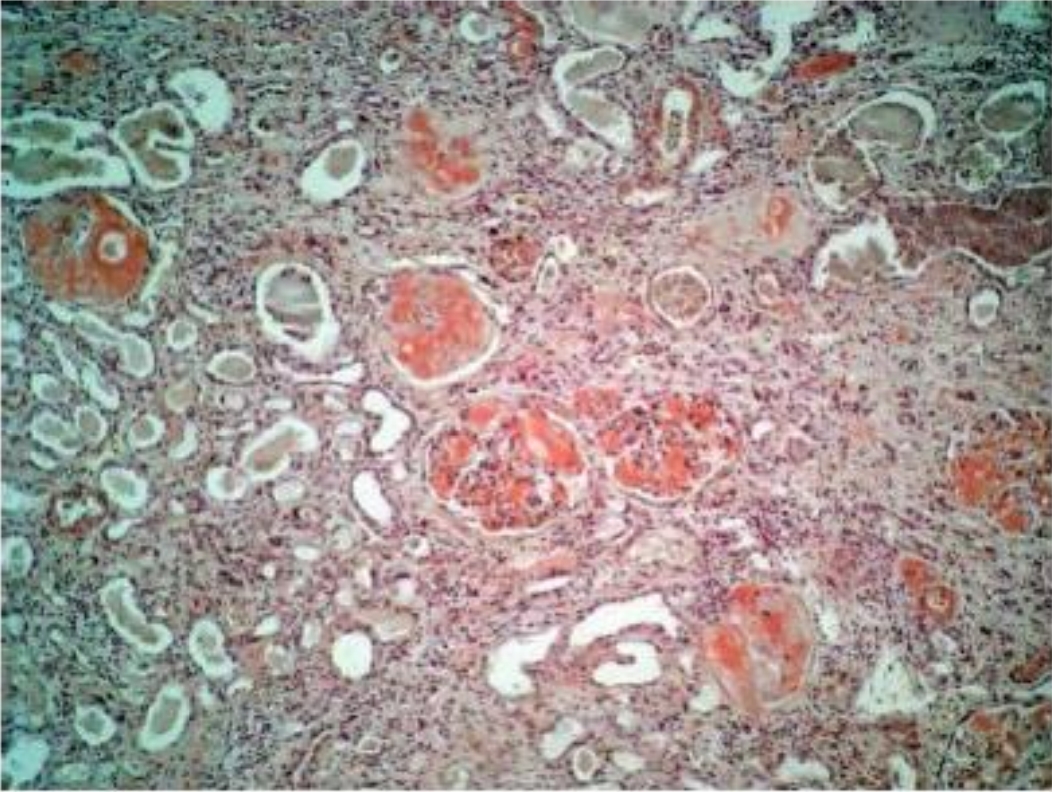

1. Congo red and haematoxylin

2. Kidney

3. Deposition of red stained amyloid in glomerulus, vessel walls, basal membrane of renal tubules and stroma.

4. Amyloidosis of kidney

5. Chronic infections, non inflammatory diseases tumors